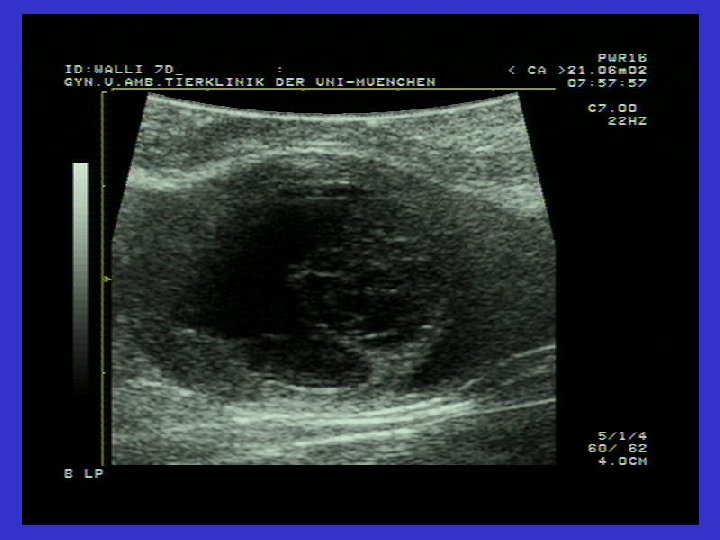

Graaf follikülü ve Follikül Theka kistlerinin karşılaştırmalı ultrasonografik görüntüsü

Ovaryum luteal kistlerinin ultrasonografik görüntüsü Solda ovaryum luteal kisti (31 mm). Gri Hipoekojenik alan çepeçevre seçiliyor.